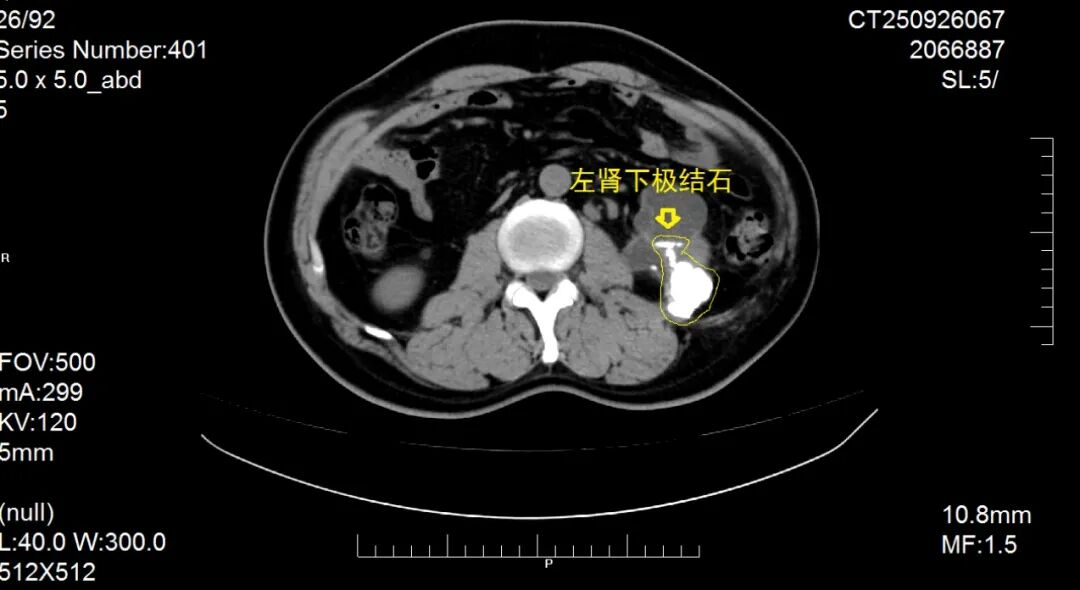

患者因“反复肉眼血尿1月,再发加重1周”入院,经系统检查确诊为复杂性肾结石

该患者结石体积大、负荷高,且合并肾内结构变异,常规微创治疗难度极高。科室团队经全面评估后,决定另辟蹊径,摒弃微创手术需反复多次取石的不足,采用传统的开放肾盂肾实质切开取石术。